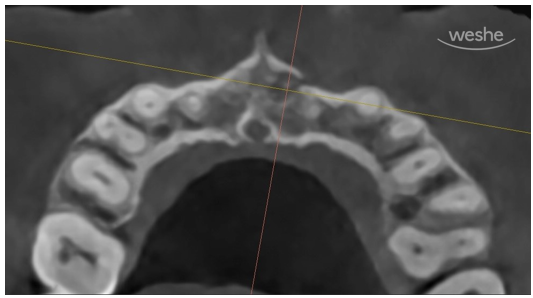

CT 사진입니다.

환자의 머리 위에서 바라보고 있는 방향입니다.

무엇이 보이나요?

노란선은 우리의 잇몸뼈 바깥경계선을 따라 그린 것입니다.

X-ray상에서 진한 흰색선으로 보이지요.

다른 부위에서는 잇몸뼈(치조골)가 연속적으로 잘 이어져 있는 반면,

빨간색으로 표시된 부위에서는 뼈의 윤곽선이 뚜렷하게 끊겨 있는 모습을 볼 수 있습니다.